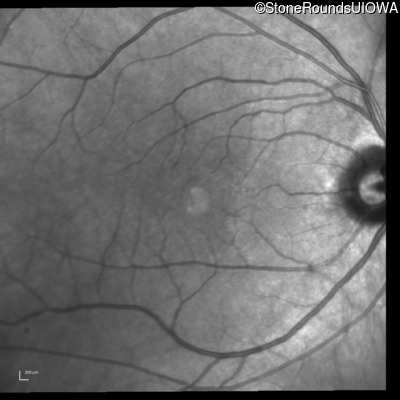

Infrared Fundus Photograph - Right - 20/20

Exemplar

Infrared Fundus Photograph - Left - 20/20 -2